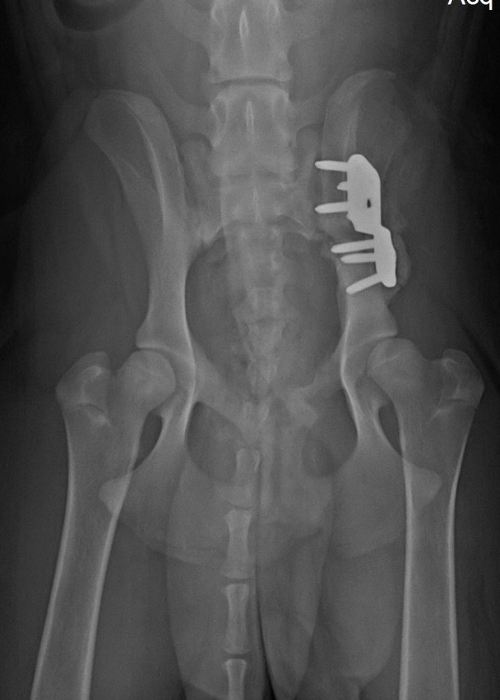

Early Diagnosis of OA Identifying DODs Canine Arthritis Resources and Education

Early Diagnosis of OA Identifying DODs Canine Arthritis Resources and Education Canine Arthritis Resources And Education Here are the best ways to manage your dog's. learn how to spot and manage osteoarthritis, the most common cause of chronic pain in dogs, from dr. arthritis in dogs | canine arthritis resources & education. canine arthritis resources and education (care) is dedicated to helping veterinarians and dog owners work to combat osteoarthritis pain. Welcome to. Canine Arthritis Resources And Education.

Early Diagnosis of OA Identifying DODs Canine Arthritis Resources and Education Canine Arthritis Resources And Education learn how to spot and manage osteoarthritis, the most common cause of chronic pain in dogs, from dr. Here are the best ways to manage your dog's. Find out the truth about arthritis,. osteoarthritis is a common problem in dogs, particularly in seniors and large breeds. Welcome to the care hub on dog arthritis for dog owners. . Canine Arthritis Resources And Education.

Early Diagnosis of OA Identifying DODs Canine Arthritis Resources and Education Canine Arthritis Resources And Education Welcome to the care hub on dog arthritis for dog owners. osteoarthritis is a common problem in dogs, particularly in seniors and large breeds. learn how to spot and manage osteoarthritis, the most common cause of chronic pain in dogs, from dr. Here are the best ways to manage your dog's. Here's a summary of the 7 principles.. Canine Arthritis Resources And Education.

Early Diagnosis of OA Identifying DODs Canine Arthritis Resources and Education Canine Arthritis Resources And Education Welcome to the care hub on dog arthritis for dog owners. learn about the symptoms, diagnosis, and treatment options for arthritis in dogs from the akc's chief. Here are the best ways to manage your dog's. osteoarthritis is a common problem in dogs, particularly in seniors and large breeds. Find out the truth about arthritis,. learn how. Canine Arthritis Resources And Education.